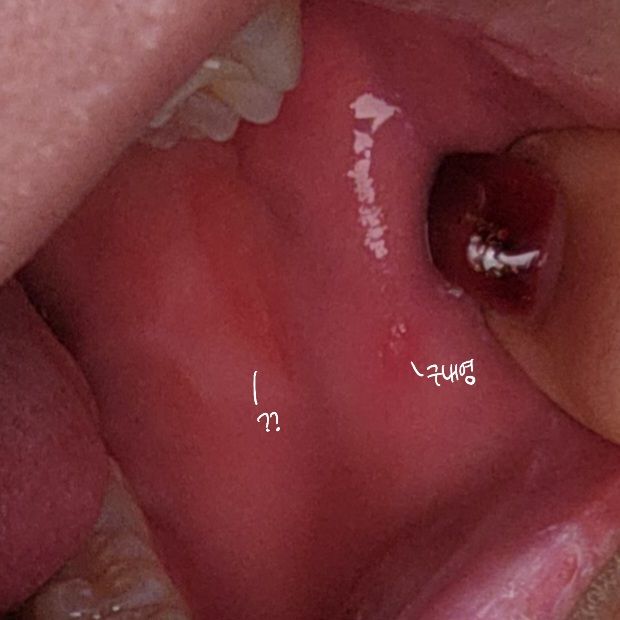

어제 오후부터 오른쪽 볼 안쪽이 사탕 오래 물고 있으면 불은 것 같은 느낌과 비슷한 느낌이었는데 오늘 하루종일 거슬리길래 확인 해봤더니 타원형의 주황색 자국이 생겼어요...

아직도 혀로 만져보면 불은것처럼 쪼글쪼글한 느낌이고 어금니에 닿을때 살짝 욱신거리기만하고 별다른 통증은 없습니다

크기가 작은 것도 아닌 것 같고 근처에 구내염같이 작고 하얀 점 하나도 보이구요

볼 안쪽에 생긴 타원형의 주황색 자국은 구내염일 가능성이 있습니다. 구내염은 입안 점막에 생기는 염증으로, 혀, 볼 안쪽, 입술, 입천장 등 어디에나 생길 수 있습니다. 구내염의 증상으로는 통증, 가려움, 따끔거림, 붓기, 붉은 반점, 하얀 반점 등이 있습니다. 구내염은 바이러스나 세균 감염, 스트레스, 영양 부족, 면역력 저하 등의 원인으로 발생할 수 있습니다. 구내염은 보통 1~2주 정도 지나면 자연적으로 치유되지만, 통증이 심하거나 오래 지속되는 경우에는 병원에서 치료를 받아야 합니다. 구내염 치료에는 항생제, 항바이러스제, 소염제, 진통제 등이 사용될 수 있습니다. 구내염을 예방하기 위해서는 손을 자주 씻고, 구강 위생을 잘 관리하며, 영양을 충분히 섭취하고, 스트레스를 줄이는 것이 좋습니다.